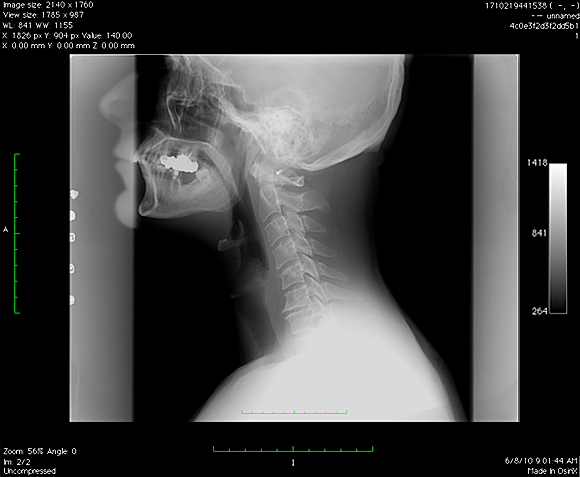

Ma tot gandesc de ceva timp la o noua schimbare pentru fotografiile de la biografie si m-am decis, intr-un fel anume, diferit de imaginile clasice, RADIOGRAFII . Radiografia este ruda cu fotografia, dex-ul spune ca ea reprezinta fotografierea interiorului unui corp opac, in special a unor regiuni din interiorul corpului omenesc sau animal, cu ajutorul razelor x, practic, conform dex-ului, va prezint mai mult… A patra din pacate nu a iesit cum imi inchipuiam aparatul de fotografiat fiind oarecum estompat din cauza unghiului prost ales, din pacate nu am putut s-o refac deoarece 3 radiografii/zi inseamna o cantitate suficient de mare de radiatii.

p.s. Am completat cu o panoramica dentara, cu un RMN la coloana si cu doua radiografii cervicale. Seria continua !